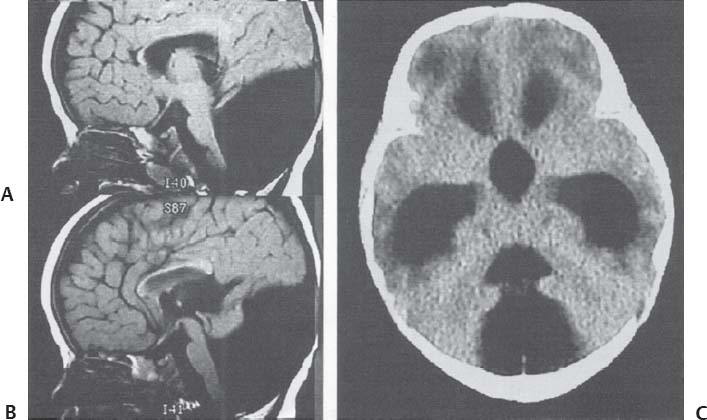

МРТ снимки мальформации Денди-Уокера